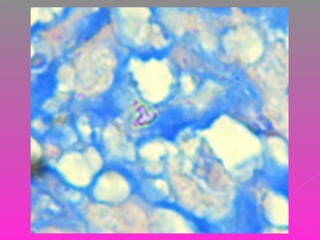

 BACILO AEROBIO ÁCIDO ALCOHOL

RESISTENTE.

 CRECIMIENTO LENTO

 SE PUEDE IDENTIFICAR EN CULTIVO,

ESTUDIO HISTOPATOLÓGICO, PCR,

EXAMEN DIRECTO DE MUESTRA

SOSPECHOSA.